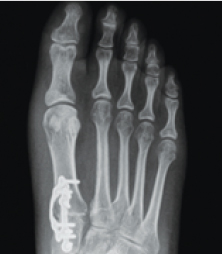

Lapiplasty® 3D Bunion Correction is an advanced surgical procedure that corrects a bunion by rotating the entire deviated bone back into its normal anatomical position. This is done using specially-designed instrumentation, naturally straightening your toe and removing the “bump” and associated pain. Innovative plating technology is used to permanently secure the unstable joint. Most patients are able to walk within days of surgery. No cast is required; allowing patients to get back to the shoe wear of their choice and activities quickly.

Lapiplasty® Patented Titanium

The Lapiplasty® Procedure utilizes two low-profile (petite), anatomically-shaped titanium plates to permanently secure the unstable foundation of your corrected bunion. This provides buttressing on multiple planes and allows you to walk within days of surgery. Think of this in terms of how a basketball player might hold a basketball. When a player tightly grips the ball with both hands, the ball is held more securely than if only one hand is used.